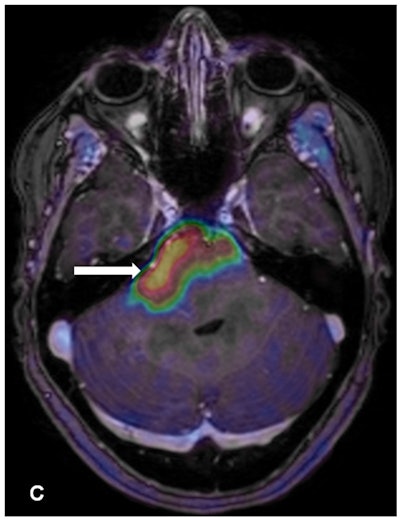

Contrast enhancement from the PET radiotracer FET highlights the brainstem glioma. Image courtesy of Albatly et al and the Journal of Nuclear Medicine.

Contrast enhancement from the PET radiotracer FET highlights the brainstem glioma. Image courtesy of Albatly et al and the Journal of Nuclear Medicine.Burger cited a few limitations of the study, including the small patient sample. The results have to be "taken with care, the Kaplan-Meier analysis especially in such a small cohort," she said.